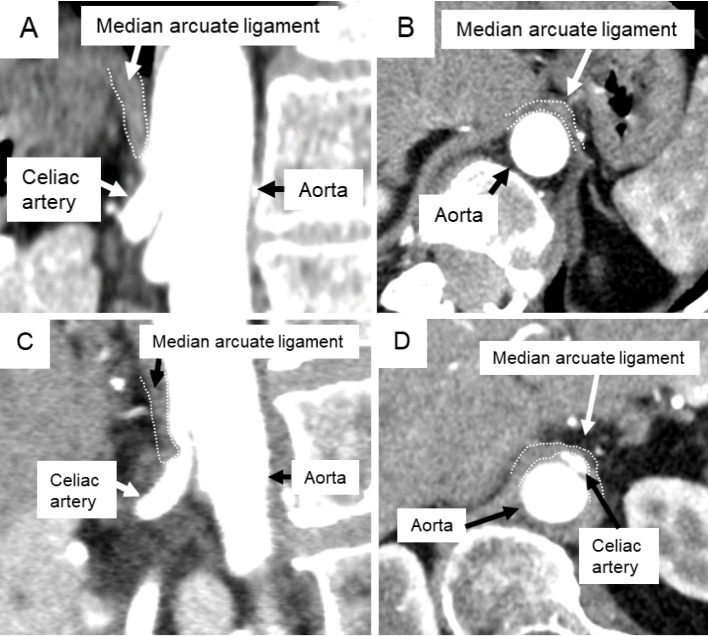

Introduction: Acute celiac artery compression syndrome occurs after corrective surgery for adult spinal deformity. It occurs due to ischemic abdominal organ necrosis, caused by compression of the celiac artery (CA) and superior mesenteric artery by the median arcuate ligament. There are no studies measuring the extent of CA or superior mesenteric artery stenosis. Therefore, this study aimed to investigate stenotic changes in the CA after adult spinal deformity surgery.

Methods: We obtained contrast-enhanced computed tomography scans for 21 pre-and postoperative patients with adult spinal deformity. Three-dimensional reconstruction computed tomography measured the degree of stenosis in the CA trunks. Stenosis was considered worse if it progressed from being less than 35% before surgery to over 50% afterward. This study investigated the relationship between worsening CA stenosis and the median arcuate ligament crossing the proximal portion of the celiac axis (median arcuate ligament overlap) or the distance between the median arcuate ligament and the anterior edge of the vertebra (DMV). Change in spinal parameters was defined as differences between pre- and postoperative values.